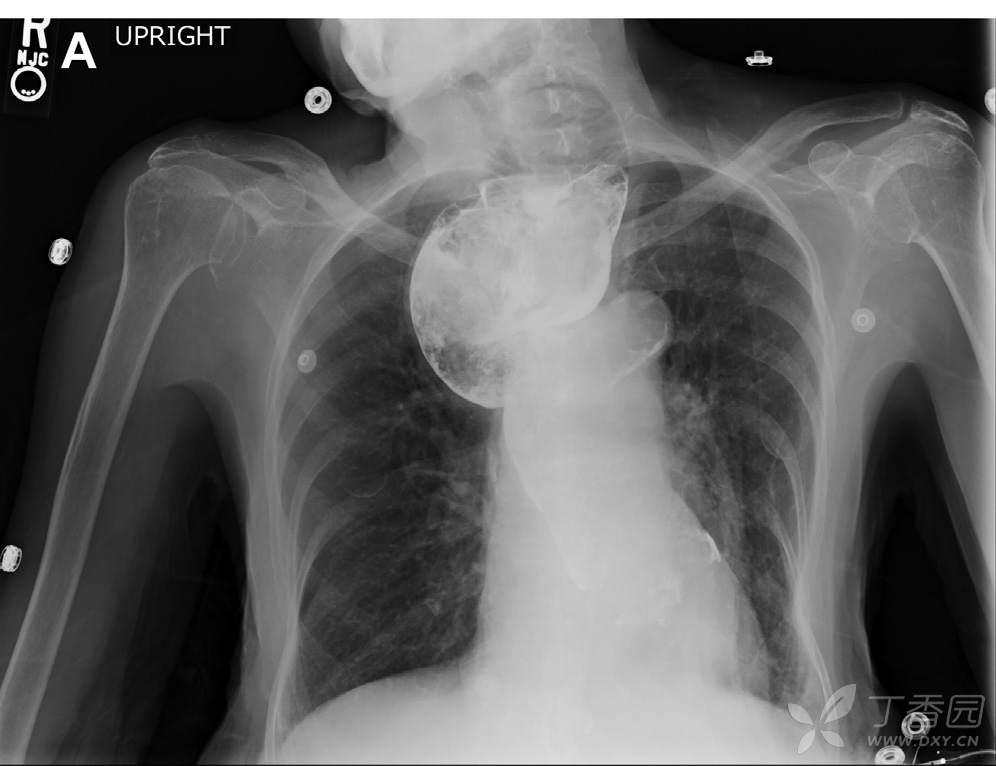

胸片可见纵隔显著增宽,双肺野基本正常(图A)。